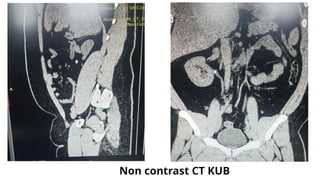

Non contrast CT KUB